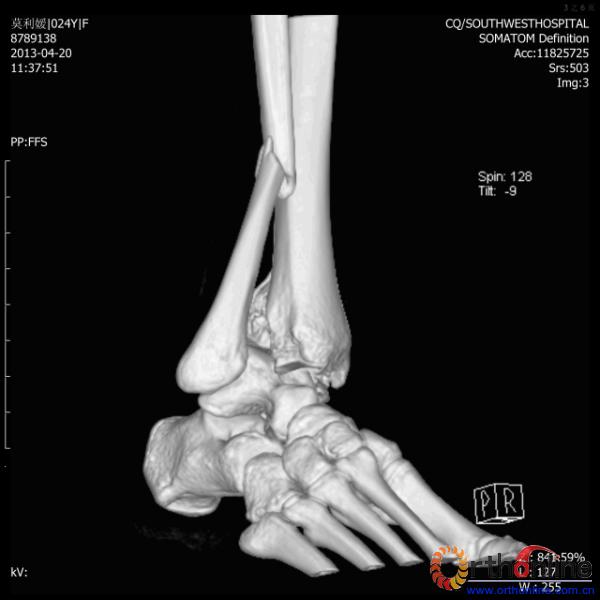

伤员和家属迅速赶到西南医院,10点关节外科段小军副教授查看伤员后急诊收入院,拍摄X片和急诊行三维CT重建检查,提示踝关节创伤严重,出现三踝骨折伴胫距关节脱位,需要急诊手术治疗。随后段教授与正在四川成都参加“汶川地震5周年灾害医学救治研讨会”的杨柳主任联系,进一步完善救治方案。地震当晚,段教授为该伤员进行急诊手术,手术顺利对复杂骨折进行了解剖复位,有效的钢板螺钉固定。术后伤员的疼痛明显缓解,复查X片,踝关节结构恢复满意。

患者术前CT(二)